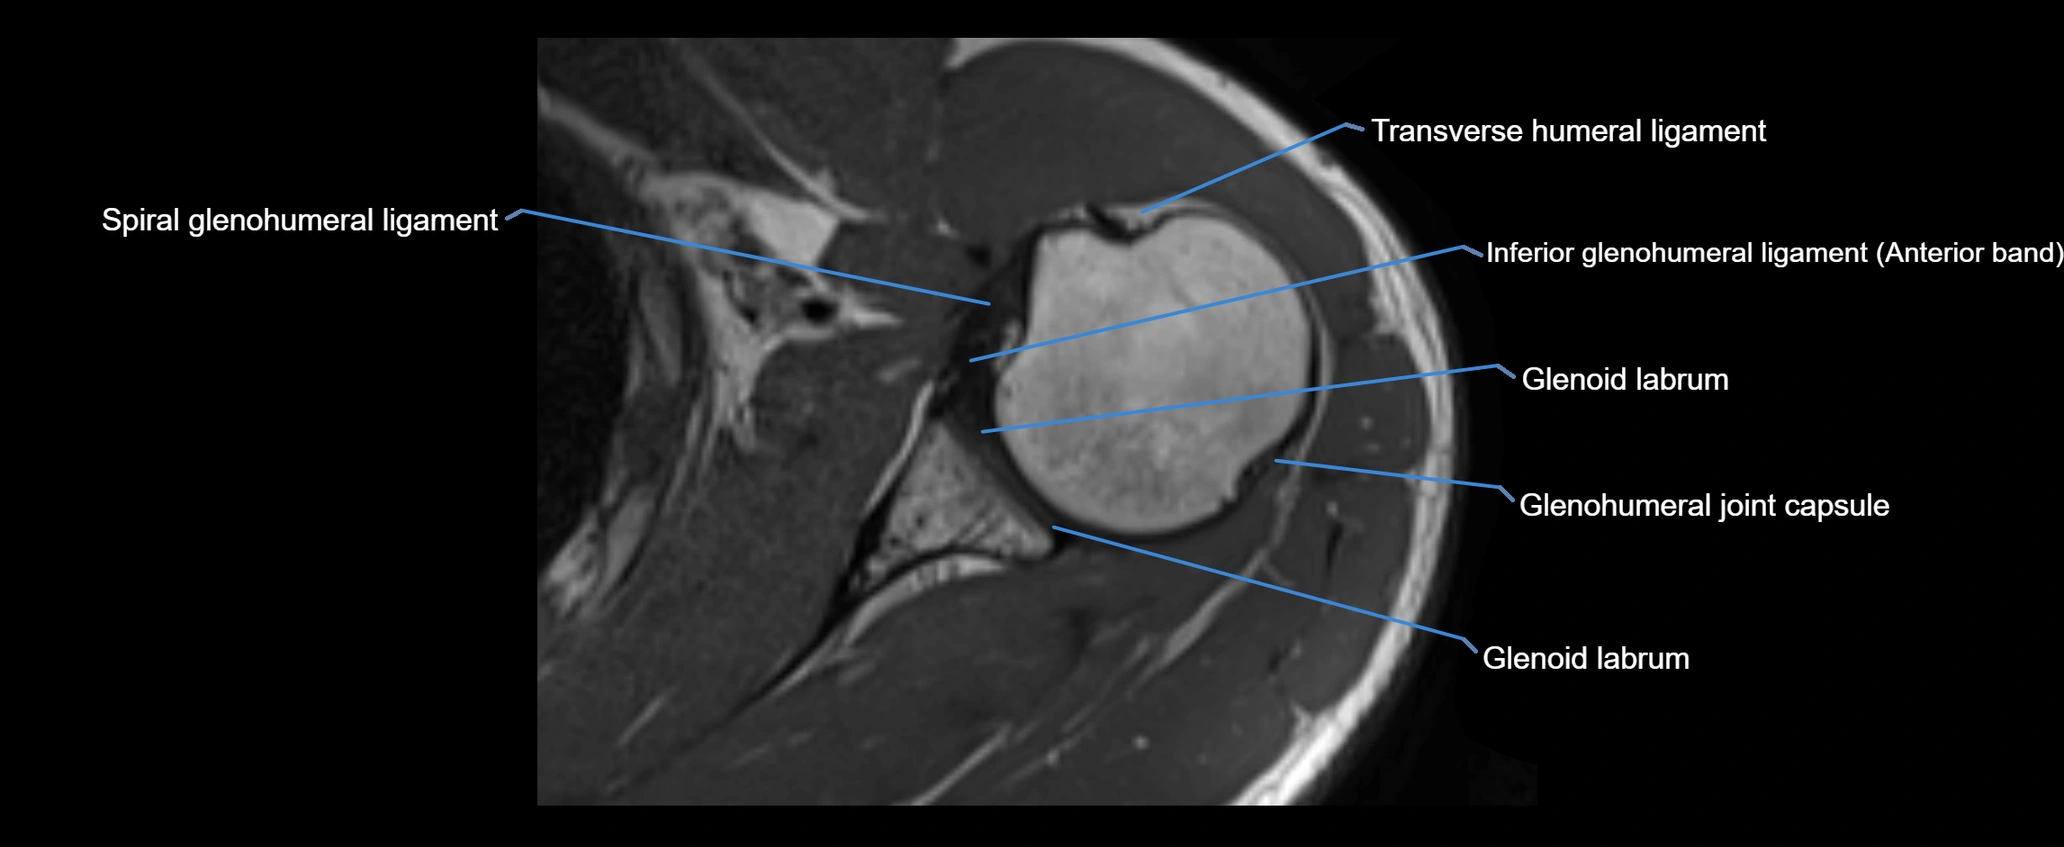

MRI Appearance

• T2-weighted images:

• Normal ligament: Low signal, homogeneous.

• Partial tear or sprain: Focal hyperintensity or thickening.

• Complete tear: Discontinuity with fluid-bright gap between clavicle and acromion.

• Associated edema: Bright signal in distal clavicle or acromion marrow.

• Proton Density Fat-Saturated (PD FS):

• Normal ligament: Low signal, uniform thickness.

• Partial tear or sprain: Bright signal or contour irregularity.

• Complete tear: Clear discontinuity with bright signal gap and joint effusion.

• Excellent for assessing joint capsule, coracoclavicular ligaments, and periarticular edema.

MRI images

image